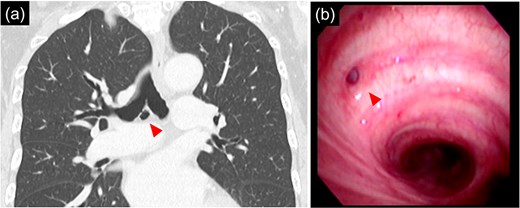

The patient was a 66 year-old woman with no history of smoking or other medical history. Chest CT showed an 18 mm nodule suspected to be a primary lung cancer in the S9 region of the right lower lobe (Fig. 1). CT-guided lung biopsy revealed lung adenocarcinoma. PET/CT showed FDG accumulation in #11i lymph node suspicious for metastasis, and the preoperative staging was c-T1bN1M0 Stage IIB. The patient was referred to the Department of Thoracic Surgery in our hospital. In addition, a 9 mm size BD communicating with the right main bronchus was observed below the tracheal bifurcation in the preoperative image (Fig. 2). Right lower lobectomy and mediastinal lymph node dissection were planned; however, because the inferior mediastinal tissue was to be dissected, a procedure for BD was also considered necessary. To achieve safe dissection around the BD, robotic thoracoscopic surgery was planned, taking advantage of the fine movement and highly flexible forceps manipulation.

(a) 9 mm size bronchial diverticulum located at the subcarinal region. (b) Bronchial diverticulum opening in the right main bronchus and two rings distal to the carina.

Bronchoscopy after intubation revealed an orifice of the BD in the cartilage of the right main bronchus with two rings below the carina (Fig. 2). First, a lower mediastinal lymph node dissection and BD were performed. The area around the BD was prone to bleeding and the lymph nodes were in close contact with each other (Fig. 3), making it difficult to separate them from the BD. After identifying and exposing the stalk of a BD, ligation of the diverticulum with ENDOLOOP® PDS II Ligature allowed for control of bleeding and the lymph nodes could be safely removed from the BD (Video 1).